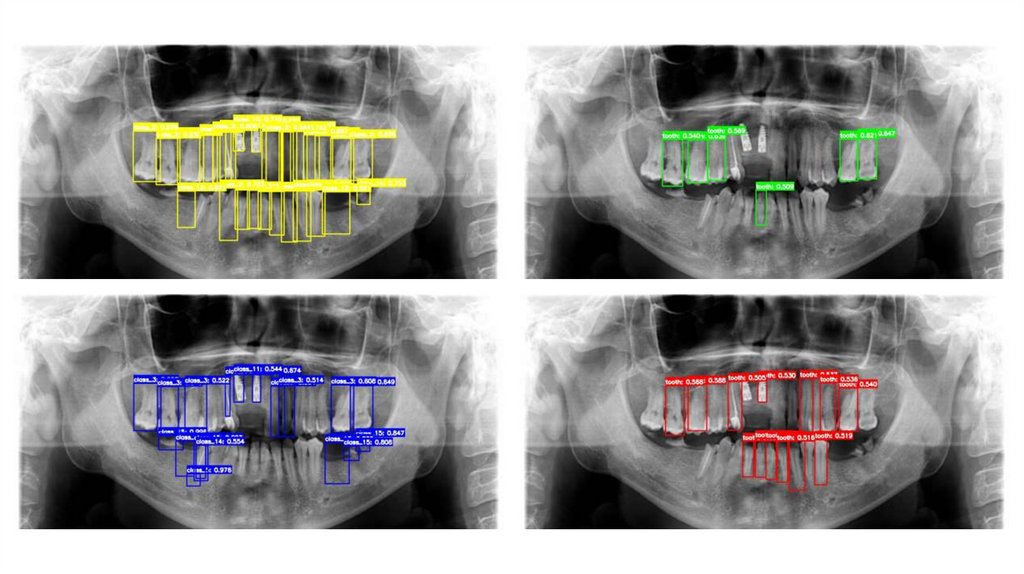

обнаружения — YOLO, RetinaNet, Faster R-CNN и Mask R-CNN —

оценивая их производительность в виде фрагментарных аннотаций,

точности и вычислительной эффективности. Наши результаты

демонстрируют превосходный баланс скорости и точности YOLO,

обеспечивающий оптимальную частоту обнаружения и эффективный

панорамный синтез на основе U-образного разреза для клинических

9. Анализ обучения модели с помощью глубокого обучения Понимание скорости обучения и выявление особенностей каждой модели в

отдельности